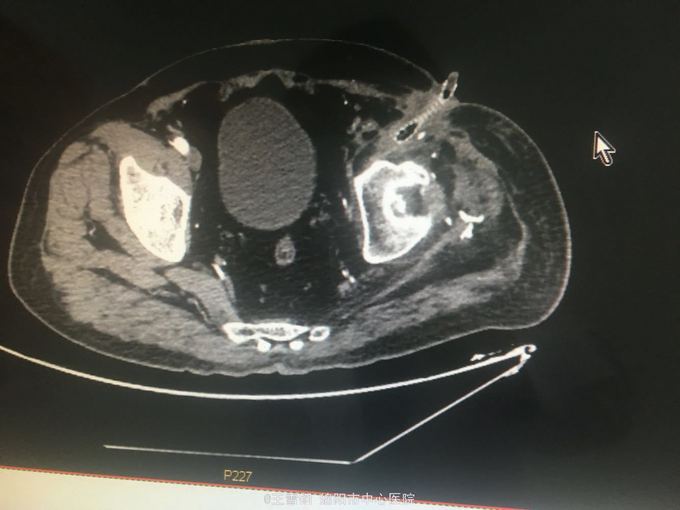

男,66岁,左下肢高位截肢术后2年,人工血管感染1年 患者2年前因外伤行左下肢高位截肢,同时伴有血管损伤,行人工血管转流,1年前腹部伤口反复出现感染,间断有脓性分泌物及血性液体流出,无明显寒战高热

下腹部可见人工血管突出体表约3cm,伴有血性液体及脓性分泌物流出 完成CT检查

左下肢截肢术后;人工血管感染; 全麻下行人工血管取出、局部清创术